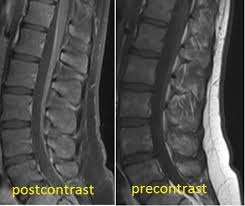

However, it can reveal nerve root enhancement and may be an effective diagnostic adjunct. The severity on mri does not correlate with severity of the clinical condition. Fisher syndrome, a clinical variant of guillain­ barre syndrome characterized by ataxia, are­ flexia, and ophthalmoplegia, brain stem lesions have been described with cranial mr.imaging (8). Its signs and symptoms are similar to those of other neurological disorders and may vary from person to person. Sagittal and axial post contrast t1 fs images shows smooth thickening and abnormal enhancement of the cauda equina and the ventral nerve roots. Moreover, gbs is also associated with any vaccination. Your doctor may then recommend: It is characterized by a triad of ophthalmoplegia, ataxia, and areflexia.

Its signs and symptoms are similar to those of other neurological disorders and may vary from person to person. Sagittal and axial post contrast t1 fs images shows smooth thickening and abnormal enhancement of the cauda equina and the ventral nerve roots. Mri is sensitive, but nonspecific, for diagnosis. The diagnosis is usually established on the basis of symptoms and signs, aided by cerebrospinal fluid findings and electrophysiologic criteria. Clinical presentation is usually characterized by rapidly progressive, ascending, and symmetric paralysis of the extremities. Scott olson / staff / getty images Your doctor is likely to start with a medical history and thorough physical examination. It is the most common cause of rapidly progressive flaccid paralysis.

On csf analysis, the cell count is normal in 85% of patients, and high protein values are seen in 64%. Sagittal and axial post contrast t1 fs images shows smooth thickening and abnormal enhancement of the cauda equina and the ventral nerve roots. Clinical presentation is usually characterized by rapidly progressive, ascending, and symmetric paralysis of the extremities. Fisher syndrome, a clinical variant of guillain­ barre syndrome characterized by ataxia, are­ flexia, and ophthalmoplegia, brain stem lesions have been described with cranial mr.imaging (8). Typically, both sides of the body are involved, and the initial symptoms are changes in sensation or pain often in the back along with muscle weakness, beginning in the feet and hands, often spreading to the arms and upper body. Mr imaging findings in eight patients (three male, five female; With treatment, people may improve more quickly. However, it can reveal nerve root enhancement and may be an effective diagnostic adjunct. Your doctor may then recommend: The most common result is a weakness and numbness that starts at the tips of the fingers and toes and spreads inward toward the body. Moreover, gbs is also associated with any vaccination. Mri is sensitive, but nonspecific, for diagnosis. Immune checkpoint inhibitors (icis) have been increasingly used in the treatment of various types of tumors with favorable results.